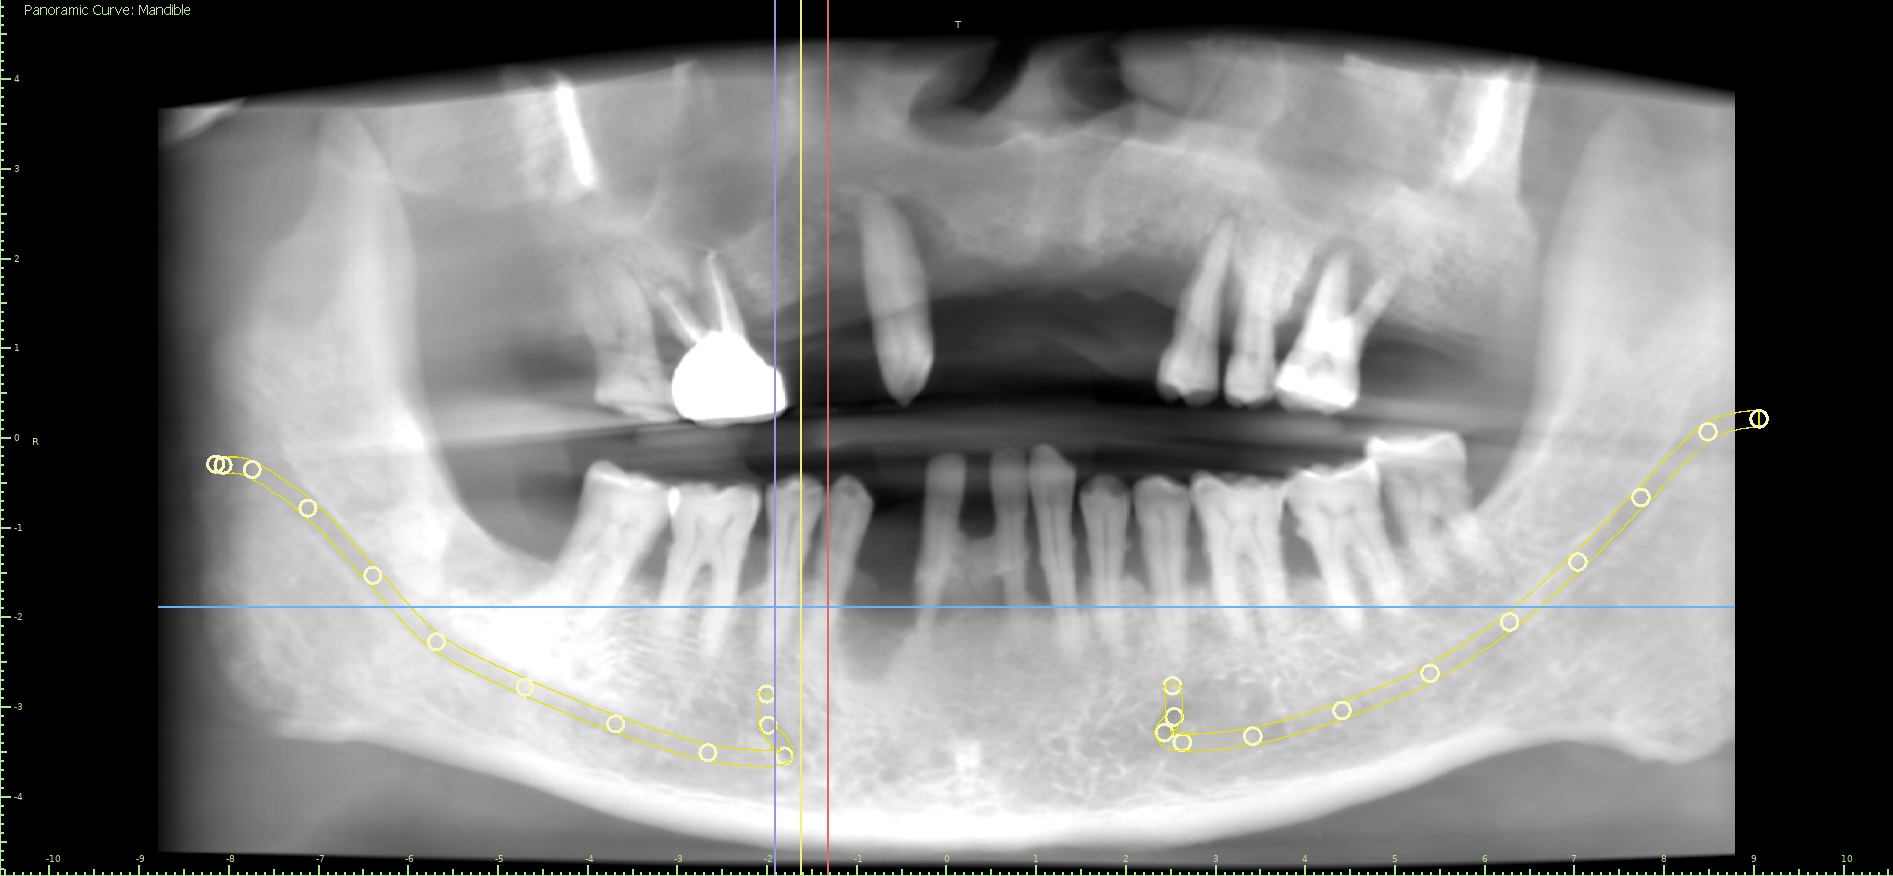

X-Ray Analysis

OPG — Before

OPG — After

Radiographic Findings

What we observe: Multiple implants placed in upper jaw (full arch) Fixed prosthesis providing continuous support Lower jaw retains natural teeth + additional implants Implants are strategically angled and distributed Good bone anchorage and stability 🧠 Simple Explanation (Patient Language) Artificial roots (implants) are placed in bone These support fixed teeth (not removable) Upper jaw is fully restored Lower jaw is strengthened with natural + implant support Now patient can chew normally